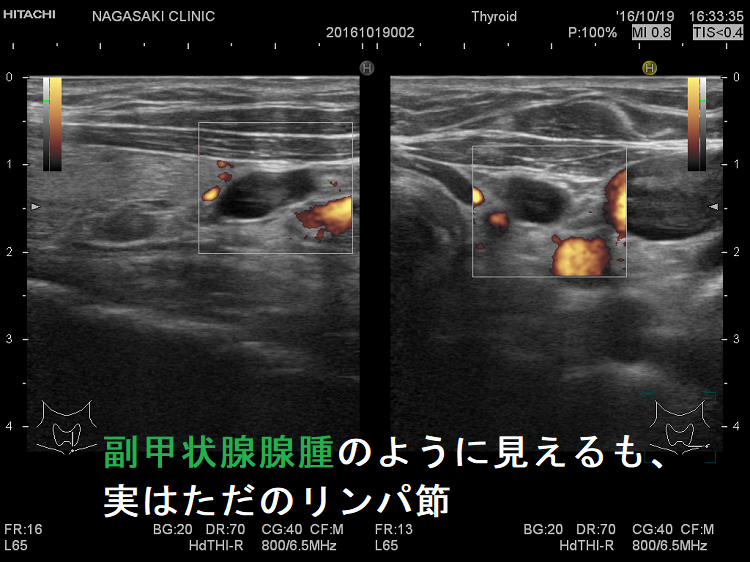

副甲状腺腺腫のように見えるも、実はただのリンパ節

副甲状腺腺腫との違いとして、リンパ節では

- 内部血流が無く

- リンパ門が存在します(ここだけ血流があります)

ケース①②